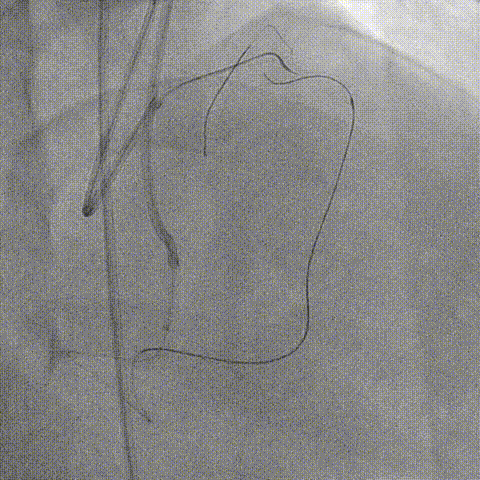

RCA AL 0.75,RCA近段 Ballon Dilatation

RCA Stent Synergy 3.5*20mm

RCA中段重度迂曲、逆向联合Expressman与Mamba,因血管迂曲 Sion无法操控,换用Suoh 03通过间隔支进入LAD

Mamba无法通过侧枝血管、深插Expressman、微导管至LAD中段、逆向先后尝试Judo 1, Judo 3, Judo 6, Gaia 3, CP 12

因血管钙化严重、导丝前进困难

最终逆向更换Judo 6,但导丝仍进入内膜下、在逆向导丝指引下,正向选择Judo 6、LAD近段严重成角,最终Judo 6 在LAD中段与逆向Judo 6靠近

尝试反向CART技术,但1.5mm球囊无法进入严重钙化段,在正向Expressman支撑下,先后使用1.25mm, 1.0mm球囊,最高24atm

再换用2.0, 2.5球囊扩张、但仍无法完成AGT技术,遂使用3.0球囊,最终逆向导引钢丝进入正向指引导管内

生理盐水冲洗RG3导丝(减轻导丝进入Mamba微导管手感生涩难题),顺利完成体外化